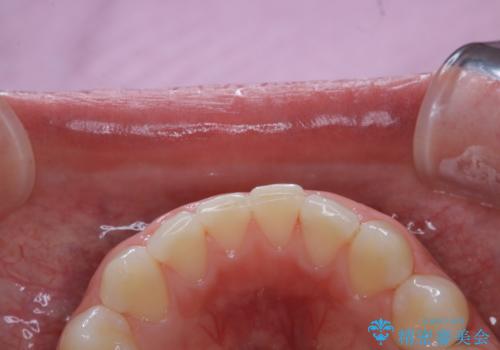

ワインによる着色・黄ばみをPMTCできれいに

- 前歯の着色・黄ばみを落としたい、とのことで来院されました。黄ばみや着色は前歯だけでなく、奥歯や裏表と全体的に付着していたため、PMTCの60分コースをご案内・ご相談し、行いました。

そのため、PMTC(歯科医院にて、専門的なクリーニング)を定期的に行うことで、着色が付きにくい歯質の強化、健康で審美的にも美しい口腔内環境を維持すことにつながります。